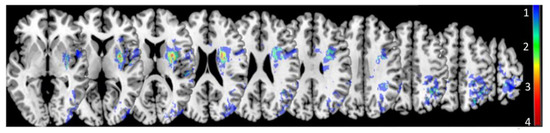

- Are distinct lesion loci observed for different behavioral impairment loci?Based on previous work and models of receptive aprosodia, distinct lesion loci are predicted for Stage 1 and 2 deficits. Maximal lesion overlap is predicted to occur within posterior and subcortical ventral stream regions (e.g., superior posterior temporal gyrus, basal ganglia, thalamus) for Stage 1 deficits and within more frontal ventral stream regions (e.g., inferior frontal lobe) for Stage 2 deficits.

4. Discussion

4.2. Lesion Contributions to Affective Prosody Recognition Training (Q3 and Q4)